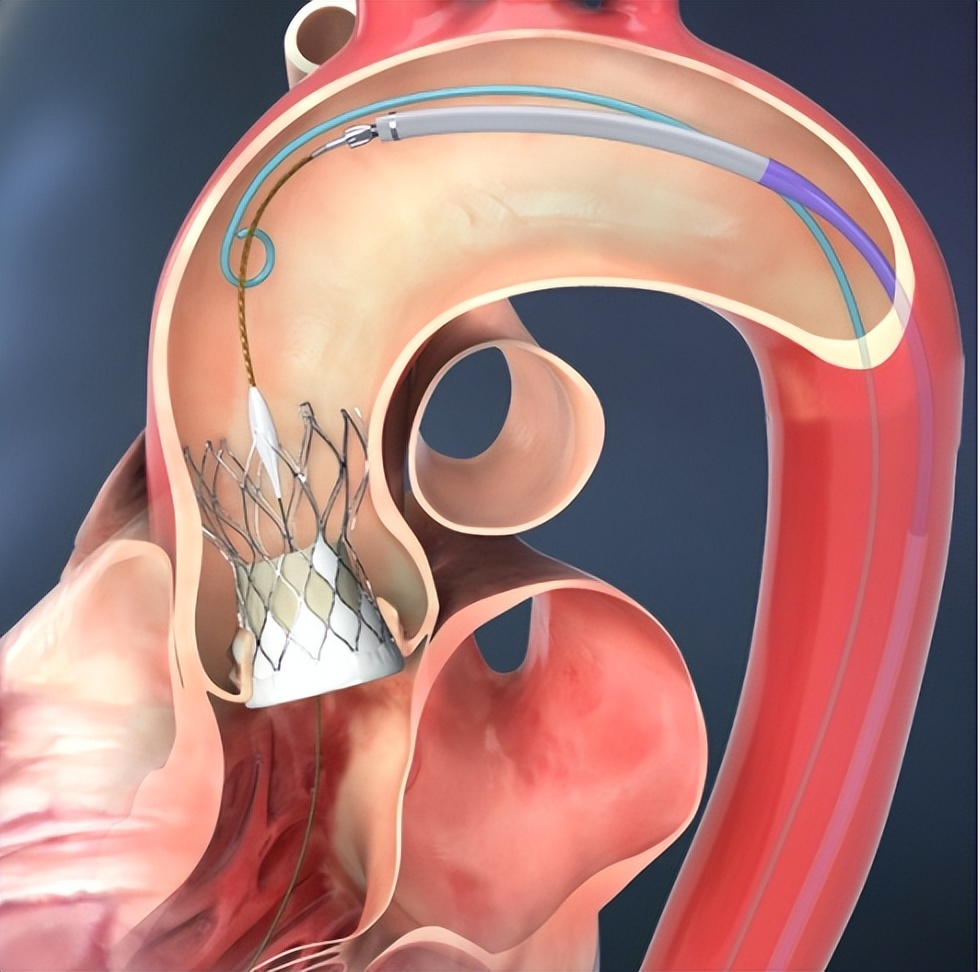

TAVR手术原理是使用微创方法,将新的人工瓣膜压缩到一根细的管子,沿着血管将这个管子输送到达心脏主动脉瓣处,然后将人工瓣膜推出或者扩开固定在病变的主动脉瓣处,以完全替代病变瓣膜的功能,起到治疗作用。由于主动脉瓣狭窄患者,其瓣膜是钙化变硬变粗糙,可以给人工瓣膜起到很好支撑固定,人工瓣膜一般不会移位或者脱落。

随着手术技术进步及人工瓣膜设计改进,目前TAVR不但可以用于治疗主动脉瓣狭窄,也可以治疗主动脉瓣反流。 近年来,TAVR技术迅猛发展,已成为高龄、高危、外科手术禁忌患者治疗主动脉瓣膜疾病的一线方案。然而,二叶式主动脉瓣的TAVR治疗仍具严峻挑战。